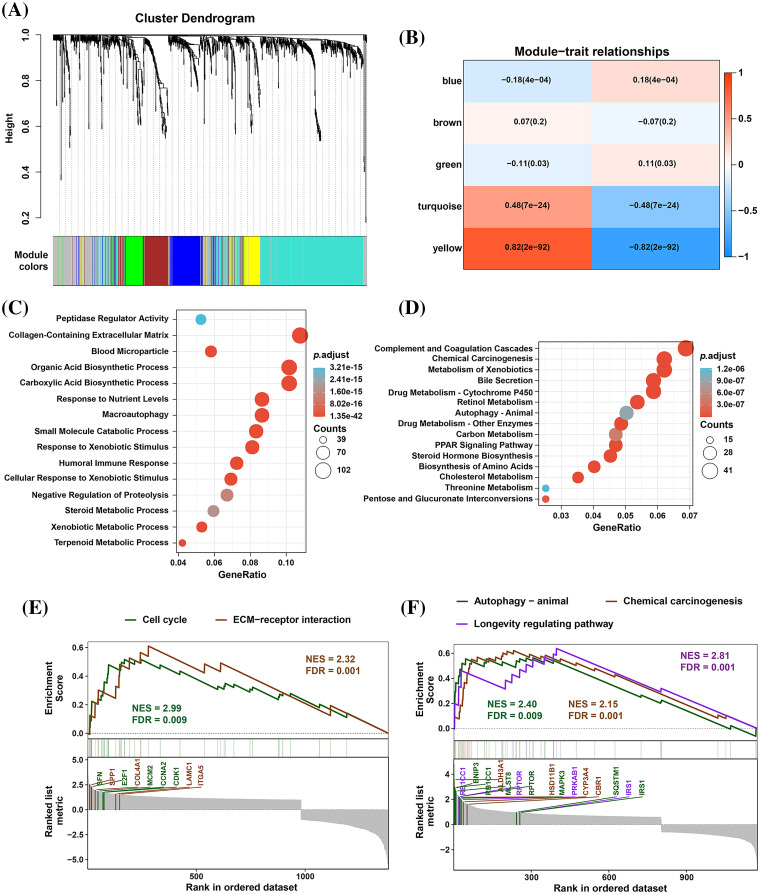

EMP2 is an autophagy-related gene in HCC

To identify significantly differentially expressed mRNAs, we performed a differential expression analysis of 374 HCC samples with high or low EMP2 expression. The analysis resulted in the identification of a list of significantly differentially expressed mRNAs. The volcano plot of the differentially expressed genes was generated to visualize the distribution of gene expression profiles (Fig. 2D). Each point on the plot represents a gene, with the color indicating whether the gene is differentially expressed. Furthermore, cluster analysis was performed on the characteristic differentially expressed genes found in the red and green regions, identifying 28 distinct autophagy-related genes. The cluster analysis results are presented in Fig. 2E. Interestingly, some of these genes, including IGFBP2 and BNIP3, are associated with autophagy [ref. 34–ref. 37]. This finding suggests a potential link between EMP2 and autophagy processes. The WGCNA method was employed to analyze the differentially expressed genes in HCC tissues categorized by high and low expression of EMP2. The hierarchical clustering was initially performed using the hclust function to eliminate outlier sample data. An appropriate soft threshold (b) was calculated as the weighting coefficient for the adjacency function through computation. Subsequently, the WGCNA package was used to compute the correlation matrix and adjacency matrix for EMP2 gene expression profiles, as illustrated in Fig. 3A. Univariate analysis identified two modules, the turquoise module and the yellow module, which exhibited significant associations with high EMP2 expression in HCC tissues (Fig. 3B). GO annotation analysis was further conducted on the 437 genes enriched in the turquoise and yellow modules, revealing key functions such as peptidase regulator activity, collagen-containing extracellular matrix, macroautophagy, small molecule catabolic process, and others (Fig. 3C). Moreover, enrichment patterns of differentially expressed genes were observed in various KEGG pathways, such as complement and coagulation cascades, chemical carcinogenesis, autophagy-animal, carbon metabolism, cholesterol metabolism, and others (Fig. 3D). GSEA pathway enrichment analysis was further performed on these differentially expressed genes. The analysis revealed that these genes were primarily enriched in two GO terms, cell cycle and ECM-receptor interaction (Fig. 3E), and three KEGG pathways, autophagy, chemical carcinogenesis, and longevity regulating pathway (Fig. 3F).